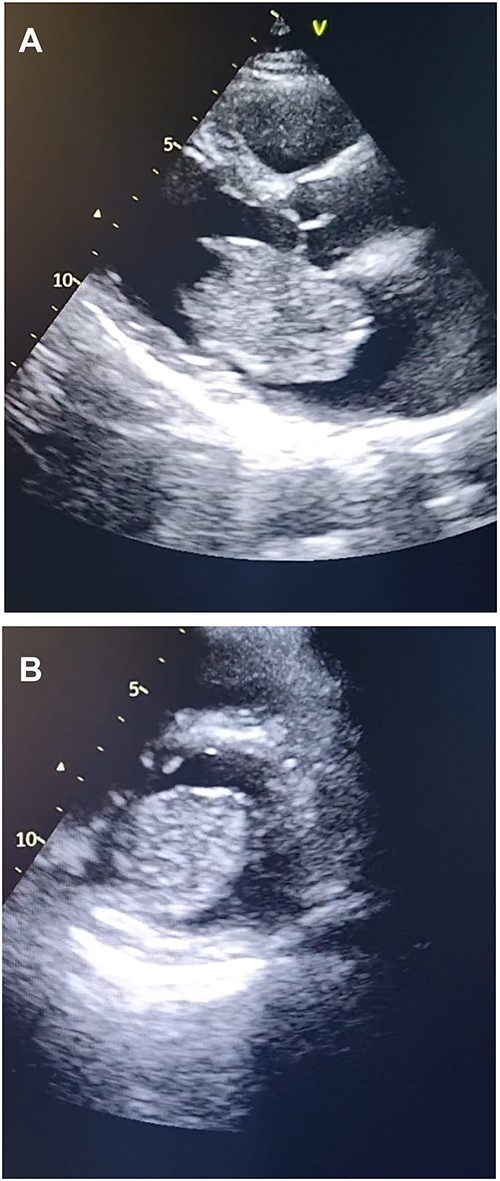

Meanwhile, transthoracic echocardiography was done to investigate the cause of loud S1 and fingers clubbing. The Echocardiography showed a large heterogeneous mass attached to the fossa ovalis in the left atrium. (Figs 1A, B and 2). This was followed by obtaining a computed tomography (CT) scan of the chest to investigate for other causes of hemoptysis. The CT scan showed no other identifiable etiology precipitating hemoptysis. Thus, it was determined that elevated pressure in the pulmonary vessels secondary to obstruction in the mitral valve blood flow caused hemoptysis in the presented case. A preoperative diagnostic coronary angiography showed normal coronaries with no evidence of stenosis.

Transthoracic echocardiography. (A) Echocardiogram parasternal long-axis view (PLAX) view showing large homogenous mobile mass in LA. (B) Echocardiogram parasternal short-axis view (PSAX) view showing Left atrial mass protrusion through the Mitral valve during diastole.